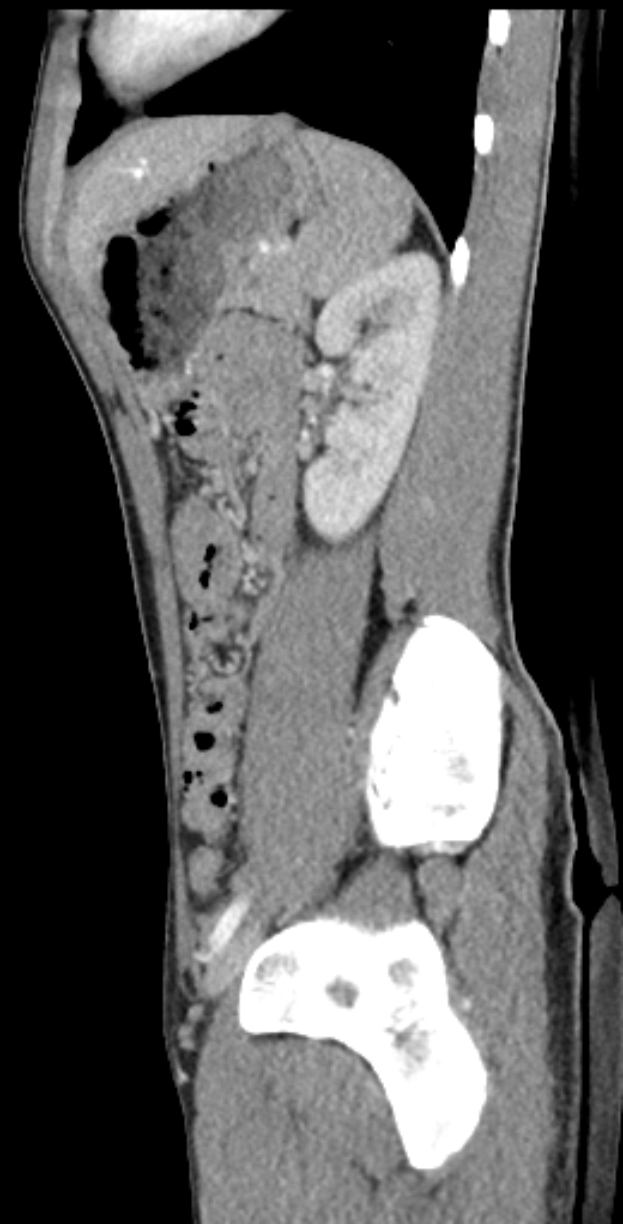

Eine MRT-Aufnahme eines Knies, die einen Bruch in der Mitte zeigt, mit einem dunklen Hintergrund drumherum.Tobias Schwarz